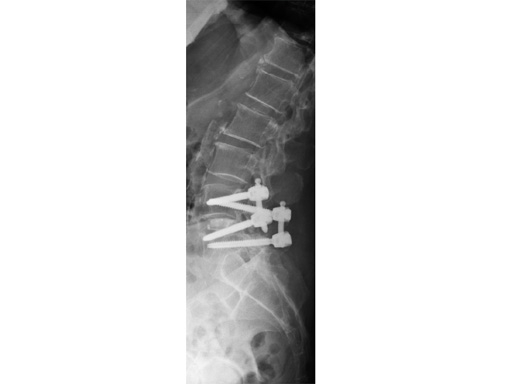

Matrix MIS allows for minimally invasive rod and screw insertion during thoracolumbar pedicle fixation. Pedicle trauma is minimized by using muscle-sparing approaches to expose patient anatomy.

This system uses cannulated pedicle screws attached to screw-mounted tissue retractors. This combination allows pedicle screw insertion and rod introduction with minimal tissue disruption. The system is applicable to single and multi-level procedures requiring posterior instrumentation.

Unique to Matrix MIS are cannulated pedicle preparation instruments, screw-mounted tissue retractors and a rod introduction instrument.